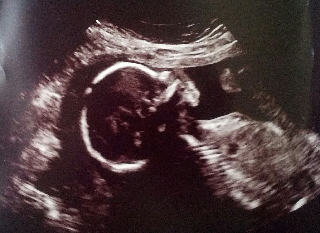

Ultrasound pics, 19 wks

Three of these 4 ultrasounds have been rendered in 3-D! I know they look strange and alien, but as a mom, I think they are beautiful. Our little girl is a bit camera-shy! And her head is perfectly round. She may have a nose like her daddy! Can't wait to see her when she is born! (Secret Spoiler: We are pretty sure we know her first name already! Brett dreamed it before we even knew she was a girl!)